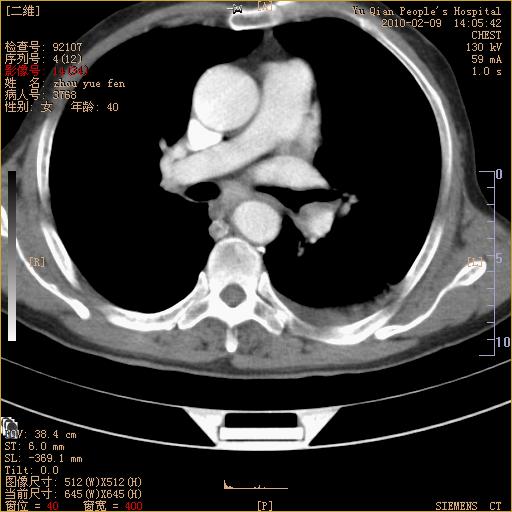

男性,73岁,咳嗽咳血数天,诊为肺ca伴左肺下叶后段阻塞性炎症、肺不张妥否?

右下肺有转移?

左下肺中央型肺癌伴结段形肺不张,左侧胸腔积液,纵隔内见部分增大淋巴结(反应性增生或转移)

左下基底干支气管明显变窄。

左肺下叶基底段支气管狭窄,左肺门增大,左肺下叶团片状病灶。中心型肺癌伴柱塞性炎症可能大,建议支气管镜检查。

左下肺中央型肺癌伴节段性肺不张,左侧胸腔积液,纵隔内见肿大淋巴结

左下基底段支气管变窄。建议进一步纤支镜检查。

1、左肺下叶后基地段肺癌伴阻塞性炎症,左下肺门淋巴结转移。2、左侧胸腔积液。